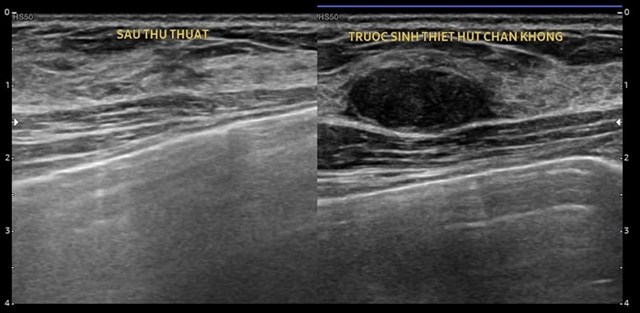

Hút VABB là kỹ thuật sinh thiết vú có hỗ trợ hút chân không, giúp lấy mẫu mô hoặc loại bỏ khối u trong tuyến vú một cách an toàn. Thay vì thực hiện phẫu thuật mở, bác sĩ sẽ dùng một kim sinh thiết đặc biệt kết hợp với hệ thống hút chân không để lấy mẫu mô. Phương pháp này được thực hiện dưới sự hướng dẫn của các công nghệ hình ảnh như siêu âm hoặc MRI.

Hút VABB được thực hiện qua các bước sau:

Chuẩn bị: Bệnh nhân được gây tê tại chỗ, vùng da được sát trùng kỹ lưỡng.

Định vị khối u: Bác sĩ sử dụng công nghệ hình ảnh để xác định vị trí khối u.

Thực hiện: Kim sinh thiết được đưa vào khối u và hút mẫu mô ra ngoài.

Hoàn tất: Sau khi lấy đủ mẫu, vùng chích nhỏ được băng lại và bệnh nhân có thể về nhà ngay.